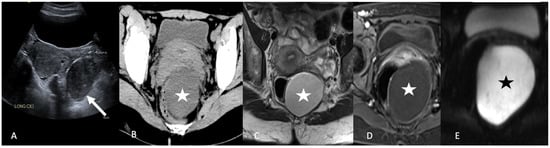

5.4.1. Appendicitis

5.4.2. Appendiceal Mucocele and Pseudomyxoma Peritonei

5.4.3. Gastrointestinal Stromal Tumor (GIST)

6. Extraperitoneal Lesions